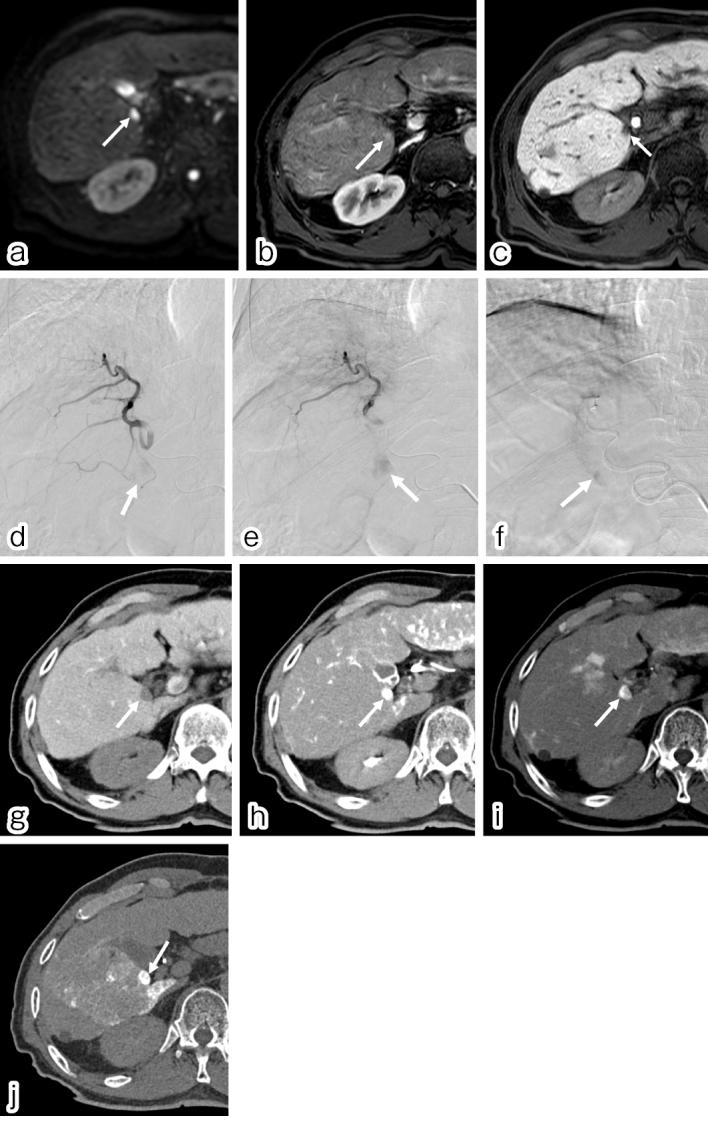

Transarterial chemoembolization is still an effective treatment option for hepatocellular carcinoma worldwide and is categorized into conventional transarterial chemoembolization with ethiodized oil transarterial chemoembolization and transarterial chemoembolization with drug-eluting spherical material transarterial chemoembolization. Several randomized controlled trials conducted in Europe have shown the equivalent efficacy of ethiodized oil transarterial chemoembolization and drug-eluting spherical material transarterial chemoembolization. However, a recent randomized controlled trials in Japan established the superiority of ethiodized oil transarterial chemoembolization in terms of complete response rates although higher liver toxicity for ethiodized oil transarterial chemoembolization. Nevertheless, the survival advantage of ethiodized oil transarterial chemoembolization is yet to be substantiated. The adverse effects of drug-eluting spherical material transarterial chemoembolization are milder than those of ethiodized oil transarterial chemoembolization, rendering drug-eluting spherical material transarterial chemoembolization an advantageous option for patients with bilobar tumors and impaired liver function/performance status. This article aims to provide an overview of these embolization techniques and a review of recent literature.

经动脉化疗栓塞术仍是全球肝细胞癌的一种有效治疗选择,可分为使用碘化油的传统经动脉化疗栓塞术以及使用载药微球的经动脉化疗栓塞术。欧洲进行的多项随机对照试验表明,碘化油经动脉化疗栓塞术和载药微球经动脉化疗栓塞术疗效相当。然而,日本最近的一项随机对照试验表明,尽管碘化油经动脉化疗栓塞术的肝毒性较高,但在完全缓解率方面具有优势。尽管如此,碘化油经动脉化疗栓塞术的生存优势尚未得到证实。载药微球经动脉化疗栓塞术的不良反应比碘化油经动脉化疗栓塞术轻,这使得载药微球经动脉化疗栓塞术成为双叶肿瘤及肝功能/体能状态受损患者的一个有利选择。本文旨在概述这些栓塞技术并回顾近期文献。